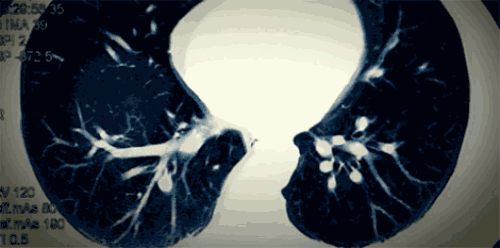

另外,人體肺部容易把百草枯中的甲基紫精分子誤認為是另一種內源性物質,將其吸收到肺泡細胞裏,導致百草枯在肺部組織中濃度異常高,引發肺部纖維化,影響氧氣跟二氧化碳的氣體交換。

一段時間後,呼吸困難、輕微乏力等症狀開始出現。慢慢地,身體器官開始潰爛,從舌頭開始,口腔、食道糜爛,肺部水腫、纖維化,喪失功能。

最終,他們往往死於呼吸衰竭或MODS(多器官功能障礙綜合徵),身心痛苦。

“醫生説我的肺,就像兩個千瘡百孔的纖維袋子”。等待宣判的過程,自己如同一頭擱淺的鯨魚。